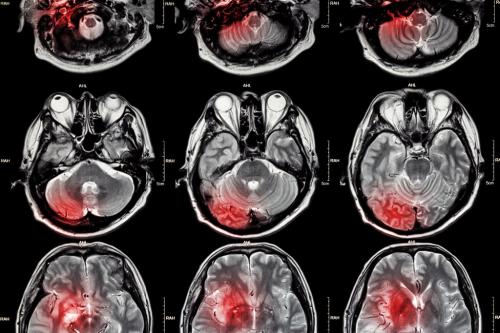

MR da vücudumuzdaki hidrojen protonları uyarılarak sinyal alınır. Sıvı yoğun ortamda hidrojen protonları hareketli olur, bu hareket diffüzyo...

MR Spektroskopi ortamda değişik doku yapılarının biyokimyasal yapıtaşları hakkında analiz yapan ileri MR inceleme yöntemidir. Hücre yapıtaşlar...